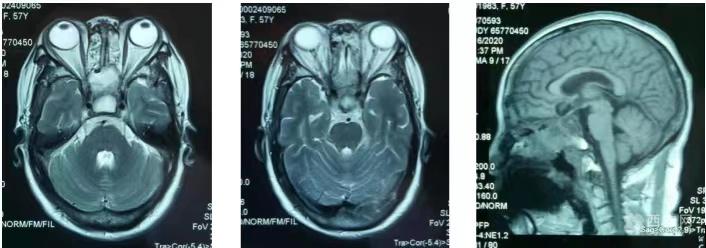

(手术后MR显示鞍区巨大肿瘤切除彻底,占位效应消除,双侧颈内动脉完好)

经过后期精心的治疗和护理,王阿姨术后恢复很快,几天后就下地活动了,而且看不出手术瘢痕。